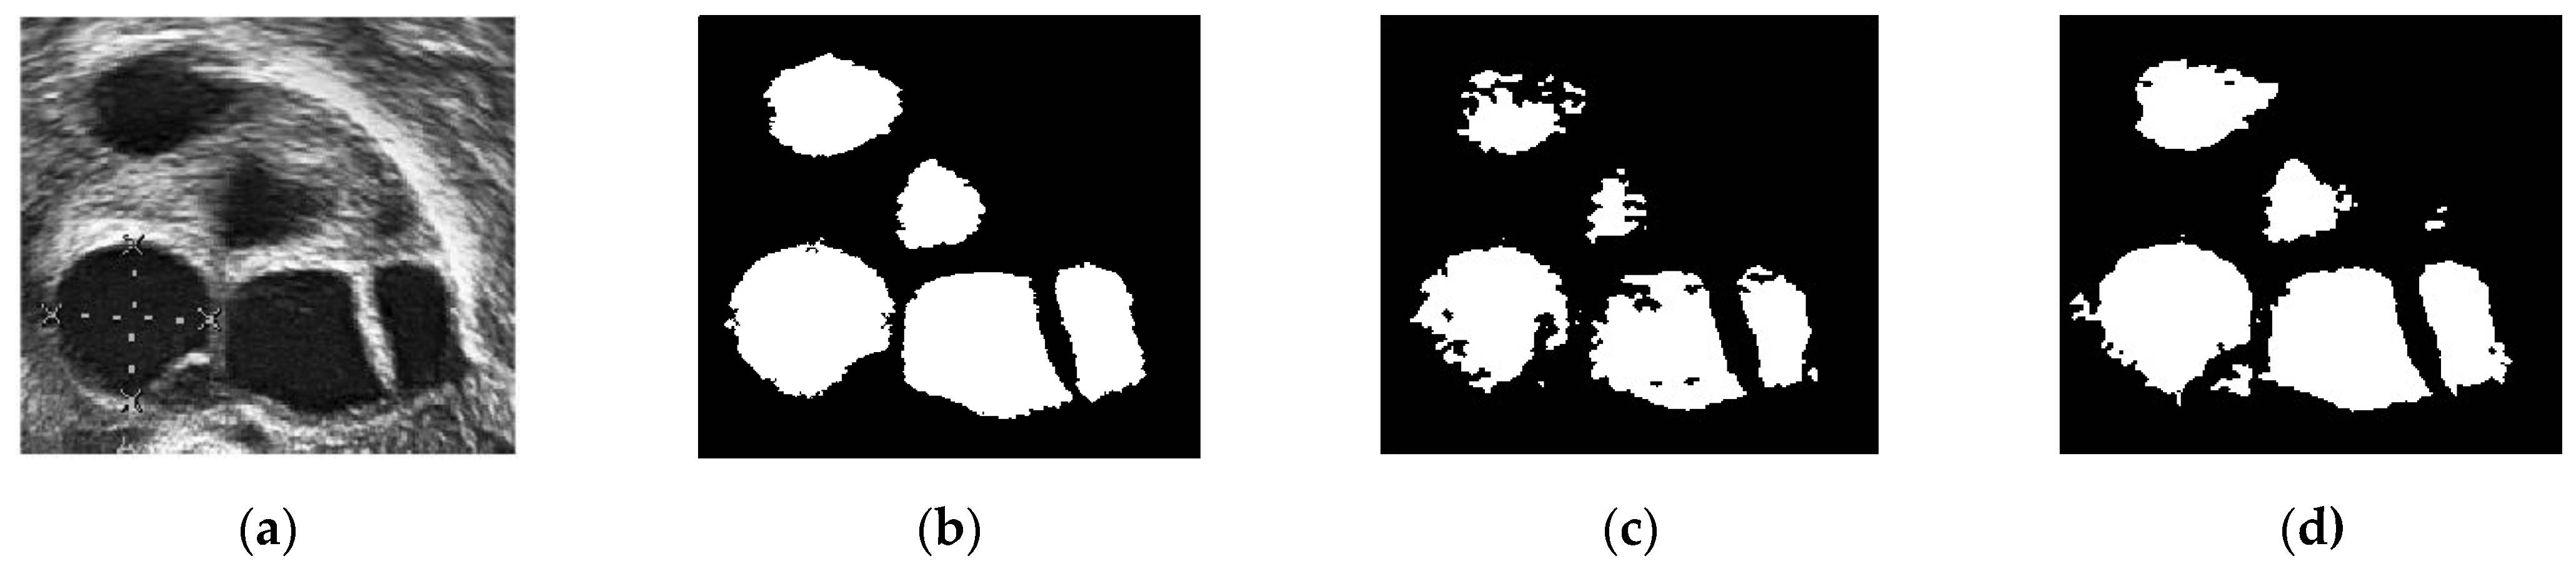

Figure 12 presents a comparison of the classical Chan–Vese and proposed methods with the follicles marked by medical experts. The original ultrasound image is shown in Figure 12a. The image is of poor quality due to speckle noise disturbances, and the boundaries between follicles are poorly visible. In Figure 12b, the red circles are follicles marked by medical experts, showing which of the dark regions are the follicles. Figure 12c shows that the classical Chan–Vese method was able to recognize all small-sized follicles in the ultrasound image. The follicles close to the rear of the ultrasound had a high dark intensity, similar to their boundaries. Otherwise, the follicles detected were relatively small in size due to the inhomogeneity of the ultrasound image. By contrast, the Chan–Vese method is suitable for homogenous images [40]. Figure 12d shows that the follicles were recognized according to the area marked by medical experts. Even though the detected follicles were nearly the same size as the marked ones, some other areas were also detected as follicles. These areas were capillaries in the ovary ultrasound that had similar intensities to the follicles in the ovary.

Figure 12.

Comparison images of different segmentation methods. (a) Original ultrasound image; (b) follicles marked by medical expert; (c) classical Chan–Vese method; and (d) Otsu thresholding and the Chan–Vese method.

Figure 13 shows another ultrasound image with three different segmentations: manual segmentation, classical Chan–Vese, and the proposed segmentation method. This ultrasound image has better image quality and lesser speckle noise reduction than the others. Figure 13a shows the original ultrasound image. Compared with Figure 12a, the speckle noise disturbances in Figure 13a do not affect the ultrasound. Moreover, Figure 13b shows the binarized follicles marked by a medical practitioner to provide a ground truth image for this study. Figure 13c,d show the difference in segmentation results. The follicles in Figure 13c, segmented using the classical Chan–Vese method, are poorly identified. The follicle boundaries may have been poorly identified during pre-processing, and without using the Otsu thresholding method, the boundary pixels have affected the segmentation results. This poor boundary detection will affect size measurements. The segmented image in Figure 13d is the closest to the manually segmented image. With the help of Otsu thresholding, the pixels have been segregated clearly to show the follicle area.

Figure 13.

Comparison of different segmentation methods. (a) Original ultrasound image; (b) manual segmentation; (c) classical Chan–Vese method; and (d) Otsu thresholding and the Chan–Vese method.

A comparison of the ground truth and segmented images is shown in Figure 12 and Figure 13. The images obtained using classical Chan–Vese method and the proposed method in Figure 12c,d and Figure 13c,d show that some false follicles were detected, because the pixel intensities in the particular area mimicked the intensities of PCOS follicles. The quantitative values of image segmentation were calculated in order to compare the effectiveness of the methods.